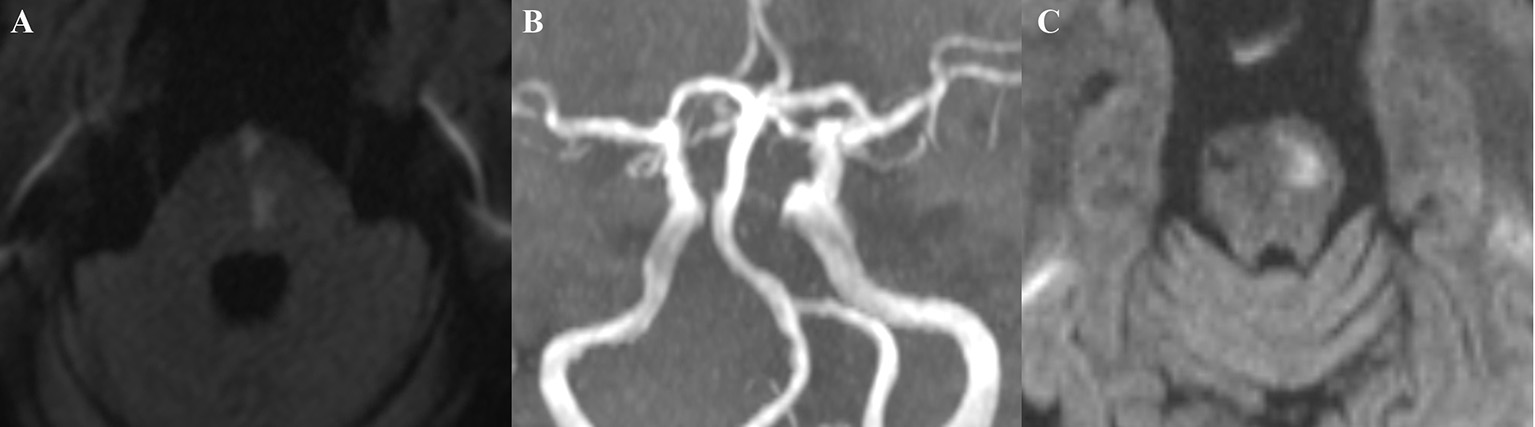

Figure 2

A typical case: This patient, a 69-year-old man with a history of hypertension and diabetes mellitus, was admitted to our hospital with right upper and lower extremity weakness for two days (Medical Research Council scale, grade IV). DWI showed left paramedian pontine infarction (middle pontine) (A); MRA did not reveal basilar artery stenosis, while BA dolichosis and moderate curvature were noted (B). The patient's muscle strength returned to normal after treatment. Four years later, the patient again developed weakness in the right upper and lower extremities, and a repeat DWI suggested the left basal infarction of upper pontine (C).